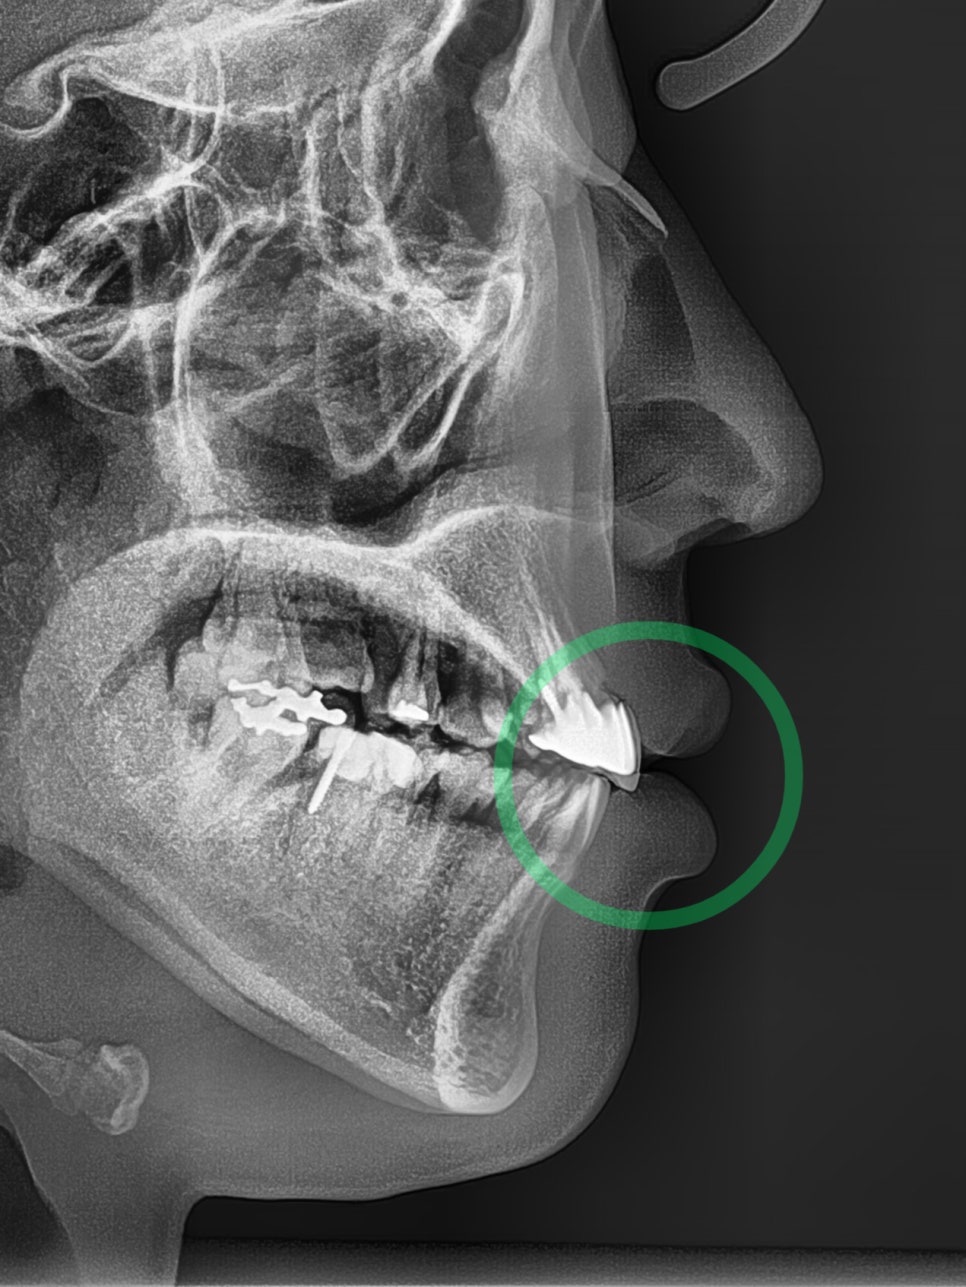

치아나 잇몸뼈 자체가 튀어나온 것을 돌출입이라 부르며, 2급 부정교합에 해당하는데요. 위아래 앞니 잇몸과 치아가 전방으로 돌출하여 웃을 때 잇몸이

안녕하세요 박현준 원장이예요. 많은 분들이 치아교정 을 받으러 오셨을 때 돌출입 을 가지고 있는 경우가 많습니다. 동양인의 특성상, 골격의 크기가

『2급 부정교합에 대해 들어보신 적 있나요?』 아래턱에 비해 위턱이 발달된 형태로 돌출된 입매를 갖고 있습니다. 교정 상담을 위해 내원하는